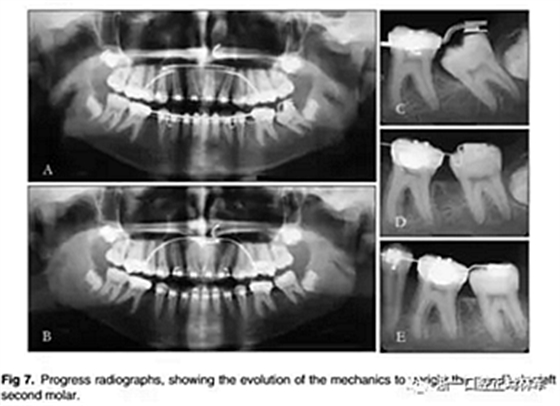

下頜左側(cè)第二磨牙直立的射線照相隨訪也完成。使用開放螺旋彈簧五個月后,該牙齒也置入不銹鋼弓絲。此時去除下頜舌弓(圖7)。